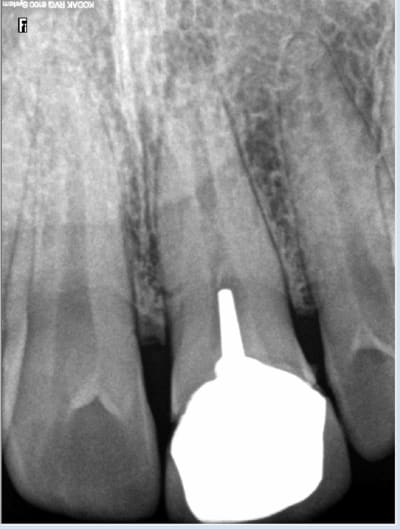

Oui validé par le CDC. Ce qui n'a pas été le cas du status complet considéré comme abusif. Faut faire gaffe aux recommandations HAS en radio quand on vérifie la tenue de son travail dans le temps. Les millisieverts doivent etre utilisés avec parcimonie, il y va de la santé du patient. -)))

Le mec, il avait une denture parfaite, la seule fois où il est allé voir un dentiste pour faire un soin, probablement suite à un trauma, on lui a fait un travail de merde. Et à la fin, celui qui rend des comptes, c'est celui qui fait un status. Vive la France!

Tu l'as un peu mauvaise. D'un autre coté ça accélère tes connaissances en indications radios. J'ai du bol en plus j'ai plus de pano sinon ca aurait été un carnage. Indication signe d'appel : trauma antérieur. -)))